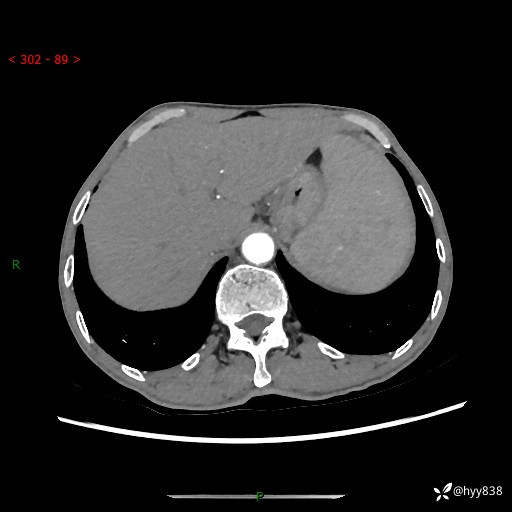

老年男性,脾大并脾脏弥漫粟粒状低密度,淋巴瘤 VS 肉芽肿 VS 血管瘤---结果公布

简要病史: 患者于3月前无明显诱因出现脾大,伴腹部轻微不适,具体不详,无腹痛、腹泻、腹胀,无头晕、头痛、乏力,无恶心、呕吐、呕血,无胸闷、气短、胸痛不适

上腹部CT平扫+增强